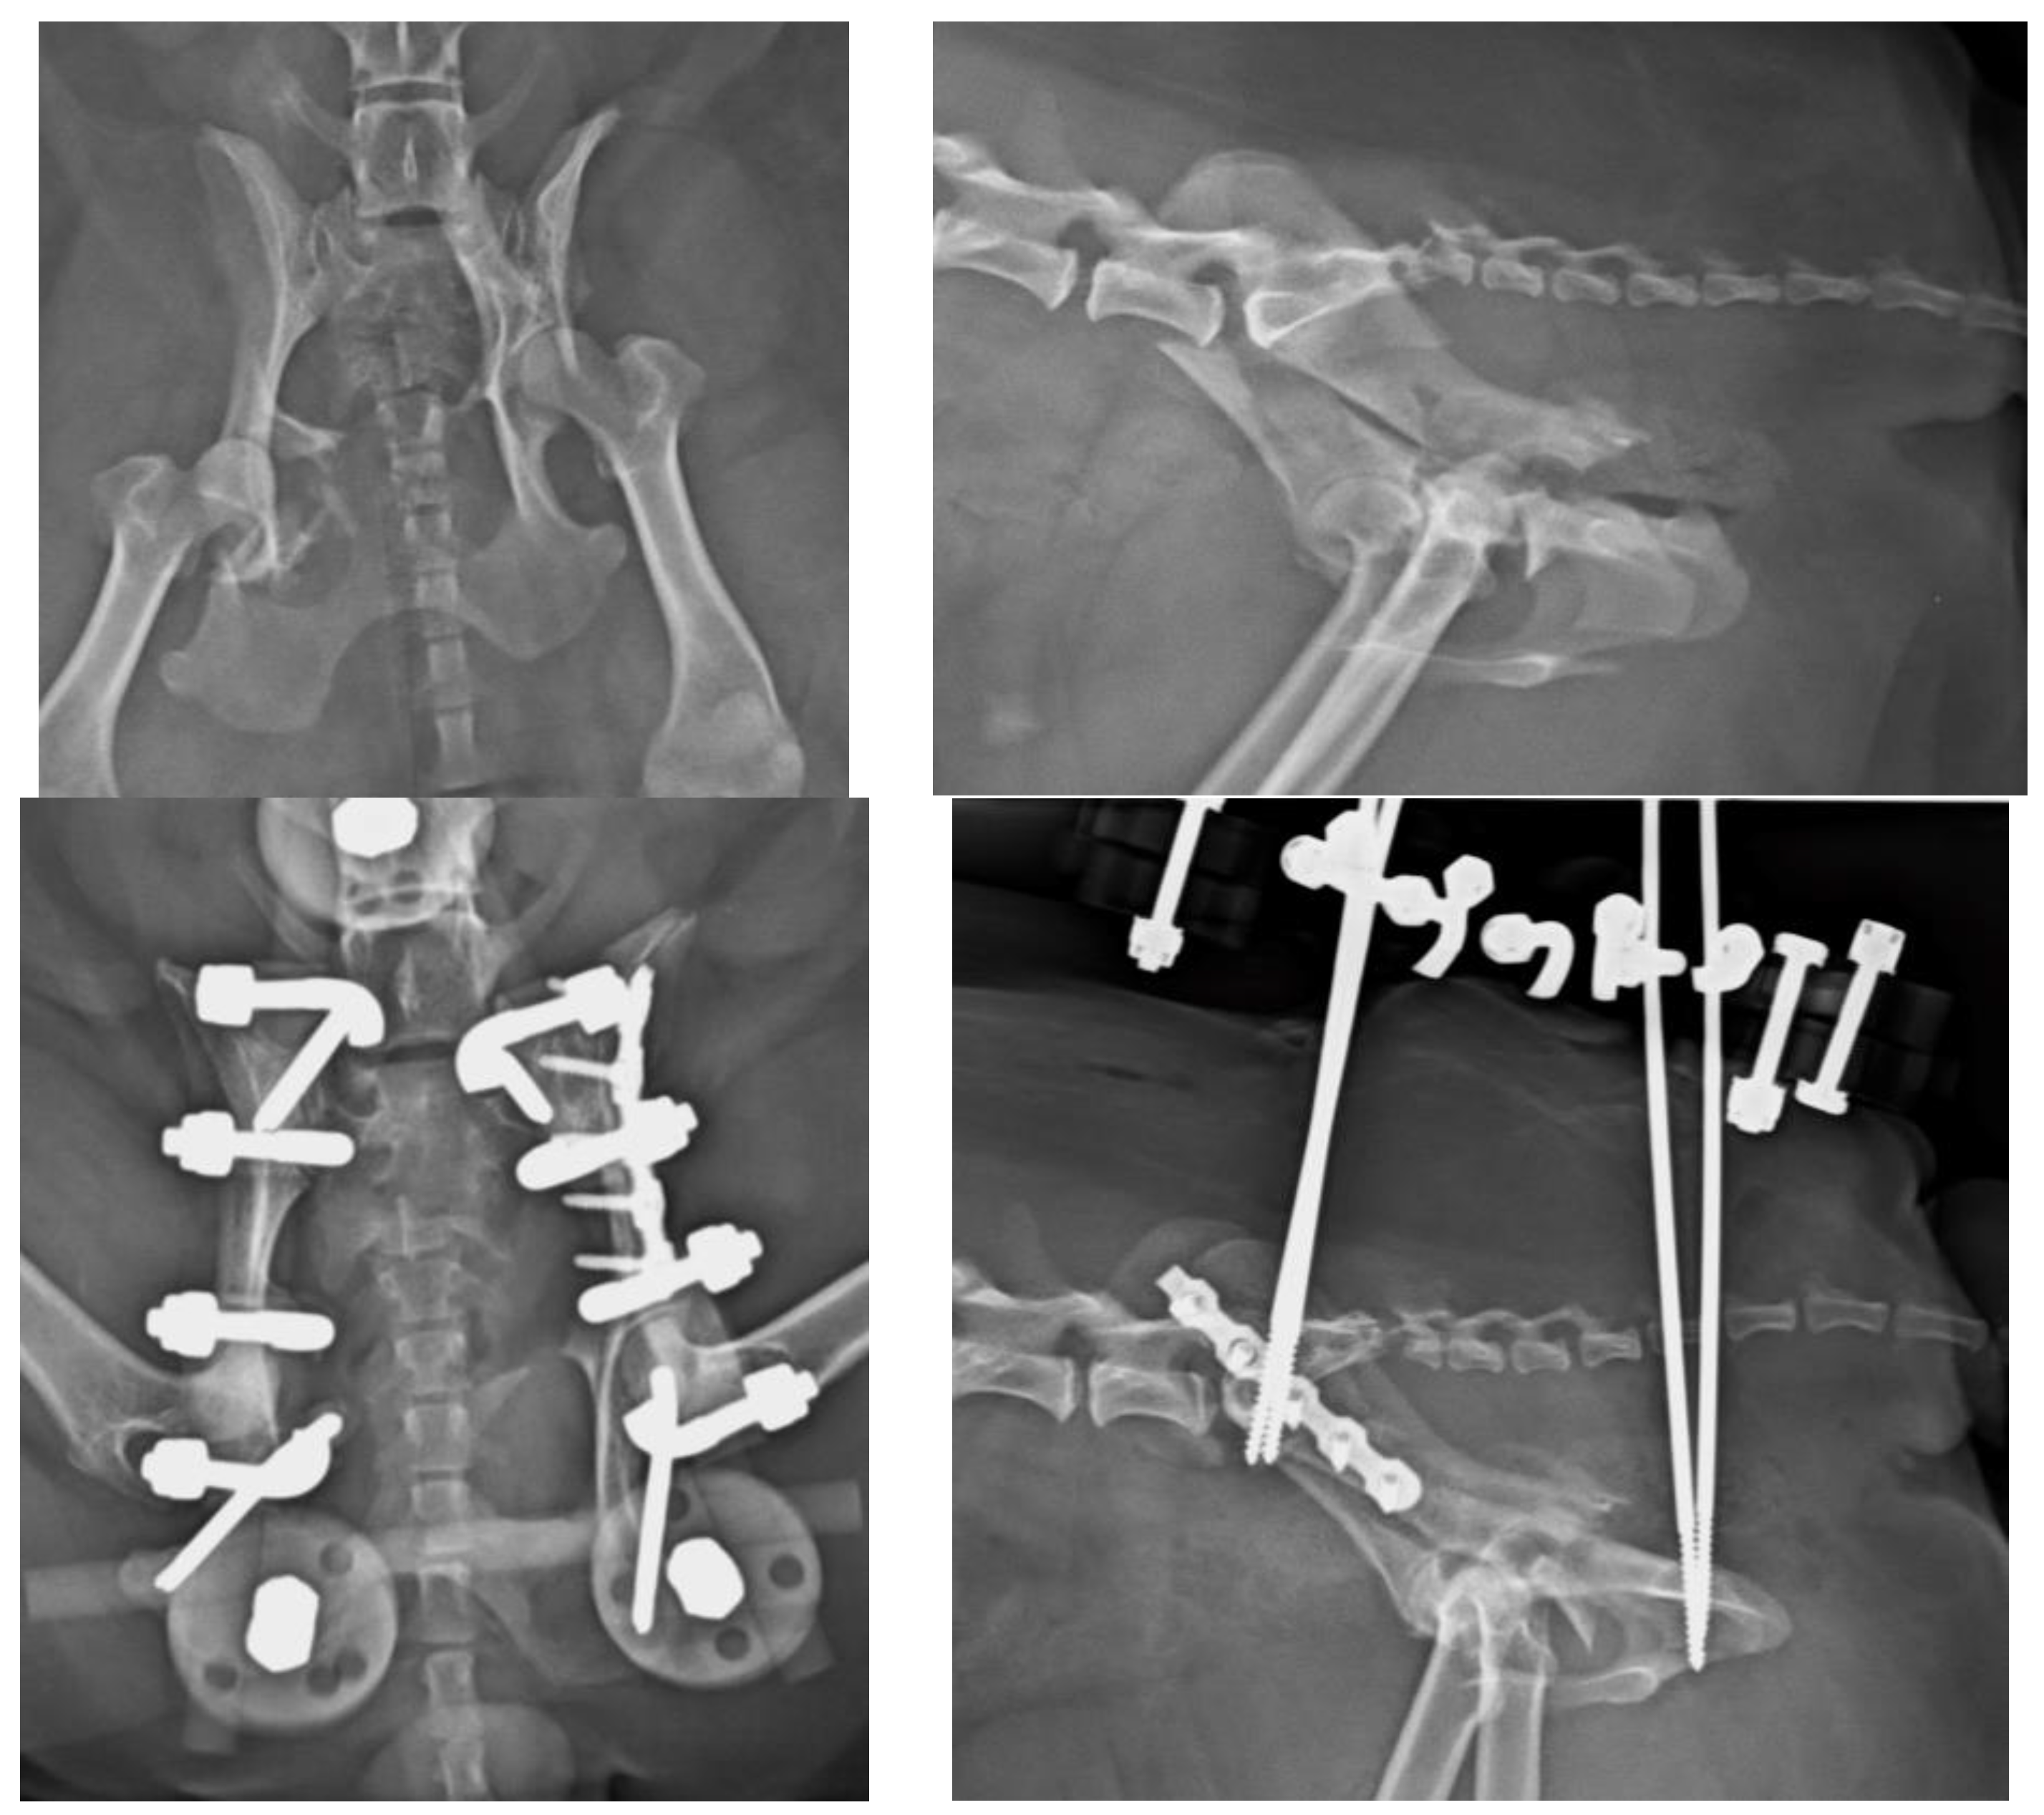

Figure 4. (Top left): Ventrodorsal (VD) projection of a patient with a fracture of the left ilium and a conminuted fracture of the contralateral acetabulum. (Top right): lateral projection of the same patient. (Bottom left): The fractures were reduced and stabilized by a type O radiolucent EF system. Note the plate used for the fracture of the ilium. (Bottom right): lateral projection of the same patient.

4. Discussion

There are few studies in the literature addressing EF applied to pelvic fractures in small animals [5], in opposition to human medicine, where its use is common in unstable pelvic fractures, especially in the early stages of treatment [13,14], due to its known biomechanical properties and its peculiar characteristics [15,16,17,18,19]. The modularity of the system and its simple application, either as a temporary or definitive method for fracture resolution, provides speed as a surgical technique, i.e., offering notable advantages in critical patients [20]. These fixators can be radiolucent, thus greatly facilitating the evaluation of healing [21]. Radiographic rechecks are easier, avoiding the need for oblique projections as usual with standard metallic EF frames (Figure 4 and Figure 5). In addition, in patients treated with fluoroscopic-assisted techniques, the interference during the procedure is considerably reduced, allowing reduction maneuvers to be performed much more easily. However, a clear downside of the use of fluoroscopy is the radiation exposure, which may be considerable in long surgical procedures. Nevertheless, in our opinion, a highly experienced surgeon can reduce considerably the amount of radiation needed.